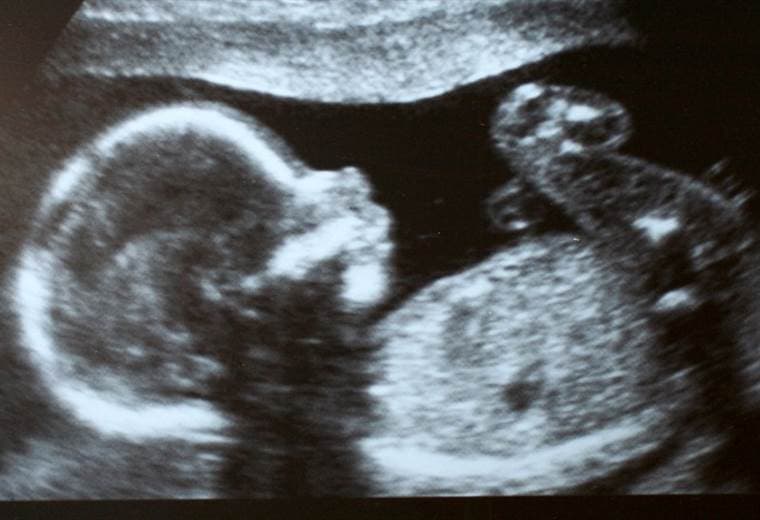

Esta joven de 23 años integra una numerosa familia en situación de pobreza dedicada a la agricultura, con una vivienda sin agua ni energía. En junio de 2020, tras ir al baño en una letrina de su casa, sin saberlo comenzó un trabajo de parto precipitado expulsando la criatura en gestación.

Según detalló la Fiscalía entonces, se trató de una niña de entre 37 y 40 semanas de gestación que presuntamente nació viva y que falleció horas después.